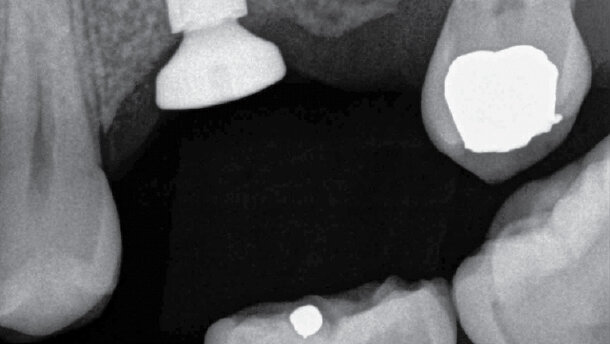

Z klinického pohledu šlo o rozsáhlý zubní kaz, nasondovaný do hloubky 3 mm, s odhaleným kořenovým výplňovým materiálem, bez provizorní výplně. Na rentgenovém snímku nebyl zjištěn žádný periapikální nález a stav kosti v okolí zubu byl adekvátní (obr. 1).

Obr. 1: Endodontická terapie provedena se zcela jasným iatrogenním poškozením a dalšími klinickými defekty

Aby bylo možné zjistit integritu struktury zubu, provedli jsme exkavaci v absolutně suchém pracovním poli zajištěném kofferdamem použitím 4,5násobného zvětšení a doplňkového osvětlení s optickým vláknem. Po částečném odstranění kazu byl vytvořen bitewing RTG snímek (obr. 2), podle něhož bylo určeno následující:

a) dno dřeňové komory bylo příliš tenké

b) bylo příliš blízko k perforaci a

c) periradikulární nebyl dostatečně silný, aby unesl definitivní náhradu